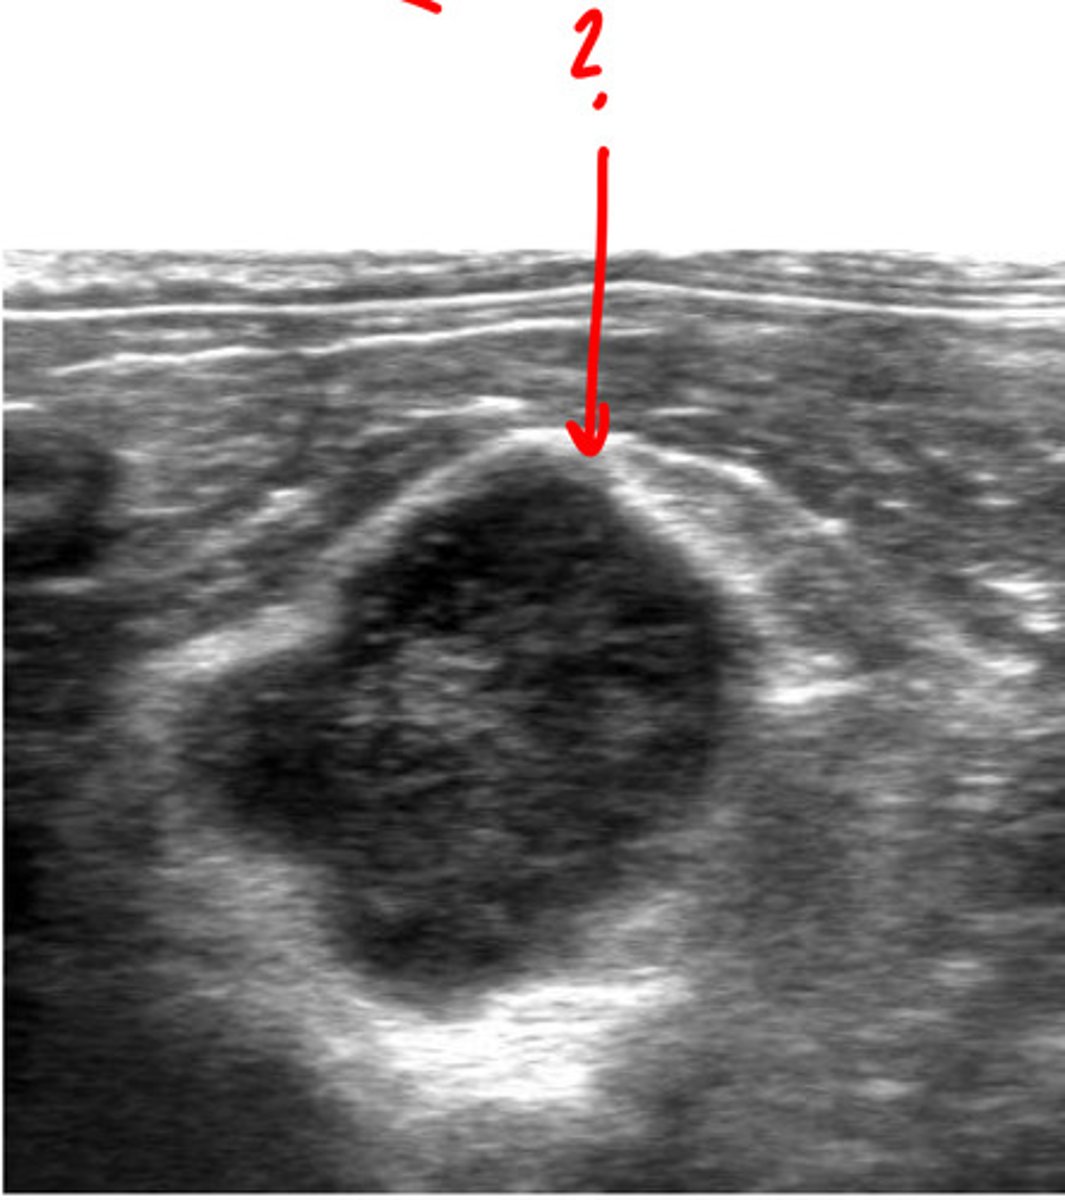

lymph node

ID structure

lymph node

what structure is this?

lymph node

ID structure

lymph node

ID